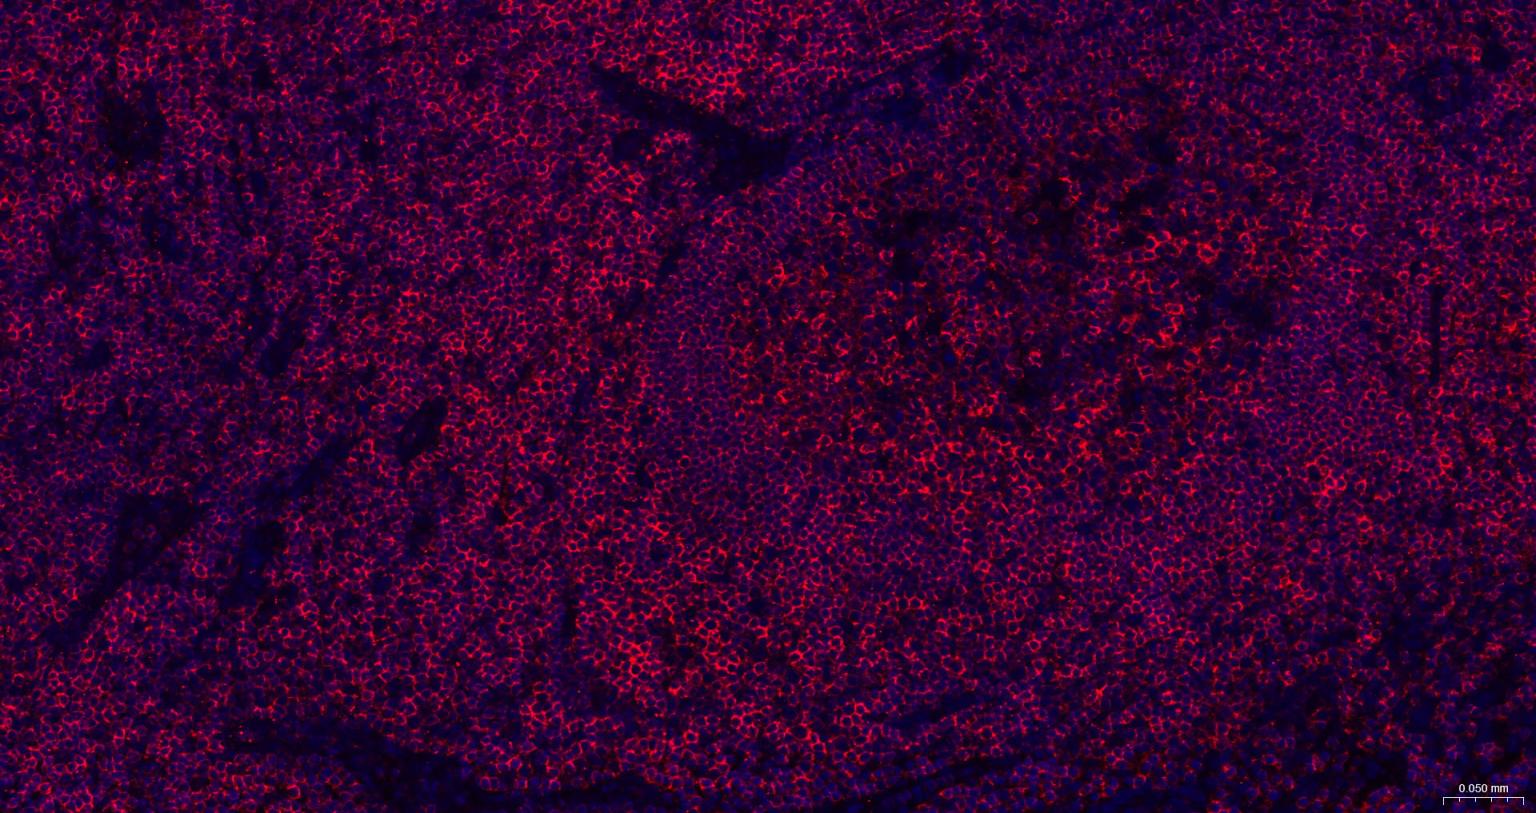

Paraformaldehyde-fixed, paraffin embedded Human Spleen; Antigen retrieval by boiling in sodium citrate buffer (pH6.0) for 15 min; The section was incubated with CD45 Monoclonal Antibody, Unconjugated (bsm-54757R) at 1:200 overnight at 4°C. Followed by conjugated Goat Anti-Rabbit IgG antibody (Red, bs-0295G-BF594), DAPI (blue, C02-04002) was used to stain the cell nuclei.

Paraformaldehyde-fixed, paraffin embedded Human Tonsil; Antigen retrieval by boiling in sodium citrate buffer (pH6.0) for 15 min; The section was incubated with CD45 Monoclonal Antibody, Unconjugated (bsm-54757R) at 1:200 overnight at 4°C. Followed by conjugated Goat Anti-Rabbit IgG antibody (Red, bs-0295G-BF594), DAPI (blue, C02-04002) was used to stain the cell nuclei.